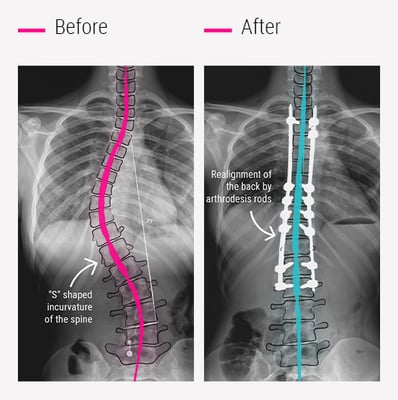

A straight spine is crucial for maintaining balance, promoting movement, and ensuring overall body alignment. However, in scoliosis, the spine curves abnormally (often in an “S” or “C” shape), resulting in uneven shoulders, back pain, and postural changes. While doctors manage mild scoliosis with observation or braces, more severe curves often require surgery to correct the deformity and prevent long-term complications.

Scoliosis surgery is a specialized orthopedic or spinal procedure that straightens and stabilizes the spine using metal rods, screws, and bone grafts. The goal is not only to correct the spinal curve but also to prevent it from worsening and restore proper alignment, thereby improving balance and lung function.

Scoliosis is a structural deformity of the spine in which the backbone curves sideways, often forming an “S” or “C” shape. The condition can develop during growth in childhood or adolescence, though it may also appear in adults due to degenerative changes or previous spinal injuries.

In a healthy spine, the vertebrae are stacked vertically, allowing balanced posture and movement. In scoliosis, the vertebrae rotate and tilt abnormally, causing the shoulders or hips to appear uneven. The severity of curvature is measured in degrees using the Cobb angle, which helps doctors decide whether observation, bracing, or surgery is required.